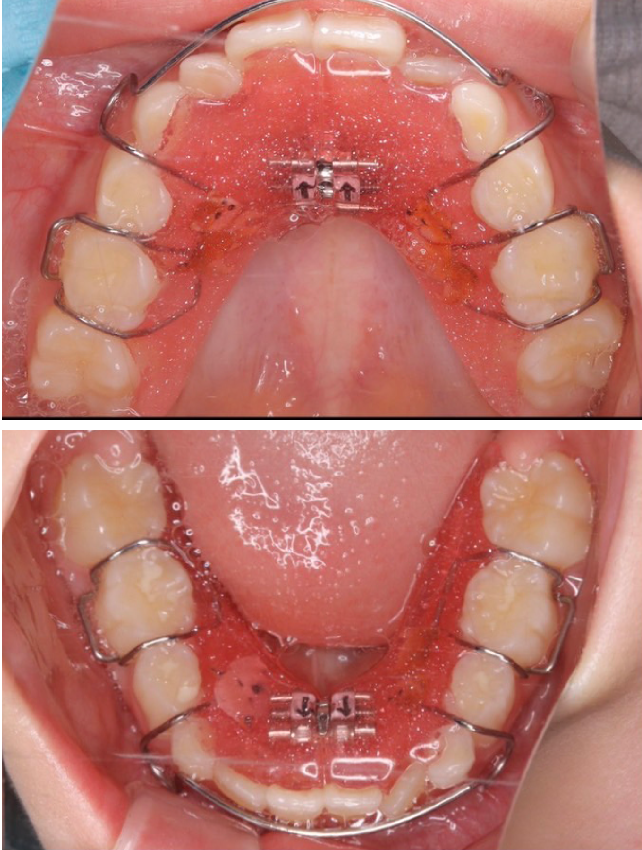

1期治療で使用する装置

拡大床

- 機能

- 横に広げるための装置

- 期間

- 6か月~10か月程度

成長期のお子さまの顎をゆっくりと広げる矯正装置です。顎の成長を正しい方向へ導くことで、歯がきれいに並ぶための土台を整えます。歯を無理に動かすのではなく、顎の成長を活かした治療のため、痛みが少なく、お子さまへの負担が比較的軽いのが特徴です。

拡大床は、多くの場合1期治療の中心となる装置で、将来的な本格矯正の必要性を減らすことにもつながります。 -

当院の症例

CASE